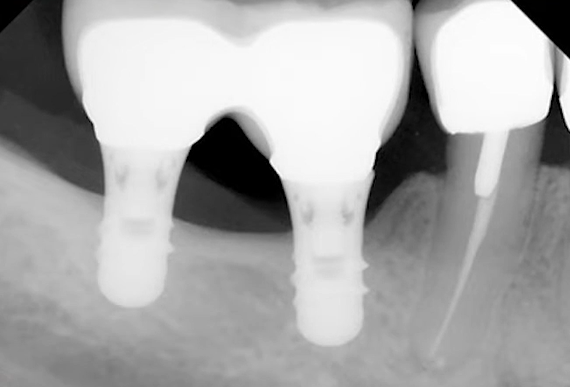

A large 6 mm diameter, 6 mm long implant with a standard thread profile was used. A standard profile means threads are sharper at the apex and become smoother toward the neck.

The implant was placed subcrestally, 1 mm below the marginal bone level. The implant apex was positioned almost at the maxillary sinus floor, as seen in the upper left slide.

Everything seemed fine: The implant was stable. However, a 12-month follow-up showed slight bone resorption, and the implant neck was exposed by about 1 mm.

Considering that the implant was initially recessed by 1 mm, the total loss is 2 mm. If the implant hadn’t been placed subcrestally, no more than 4 mm would have remained in contact with the bone, and now it’s 5 mm, which is still low, but not critically so.

- Maximize the contact area for stable restorations. A short implant should have the widest possible diameter. An implant 6 mm in diameter and 6 mm in length has a bone contact area comparable to a 4 mm x 10 mm implant.